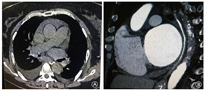

病例1患者男性,73岁。1个月前于我院行房颤导管消融术,主因"发作性胸痛伴寒战6 h"入院。患者6 h前于散步时突发胸骨后疼痛,为刺痛,吸气时加重,无放射痛,伴寒战、发热,体温最高37.5 ℃。既往有高脂血症病史10年,糖尿病史半年,陈旧性脑梗死半年。患者入院心电图示房颤心律,无明显ST-T改变,心肌损伤标志物未见明显异常,血常规示:白细胞计数(15.05×109 /L)及中性粒细胞(0.958)明显升高,D-二聚体2.102 mg/L。入院1.5 h后患者突发头晕、意识模糊,血压下降至75/50 mmHg(1 mmHg=0.133 kPa ),心电图示:Ⅲ度房室传导阻滞,下壁导联ST段弓背向上抬高,考虑"急性心肌梗死",予补液、多巴胺静脉泵入维持血流动力学稳定,以及阿司匹林、氯吡格雷负荷剂量后同时急诊行冠状动脉造影,但造影结果提示冠状动脉血管通畅,未见明显狭窄、痉挛及夹层等表现。入院第2天患者出现寒战、高热,体温升至39 ℃,伴呕吐咖啡色胃内容物300 ml,20 min后突发意识丧失。查体:血压90/60 mmHg,心率110次/min,中度昏迷,双侧瞳孔等大等圆,对光反射减弱。行头颅核磁共振成像检查显示:双侧大脑半球多发急性脑梗死。急查左心房肺静脉CT血管造影(computed tomography angiography,CTA ),结果显示:纵隔多发气体影,左心房后壁与左肺静脉交界处可见龛影(图1)。结合患者既往有房颤射频消融术病史,考虑"LAEF"可能,遂请心外科急诊行开胸探查并修补术,术中直视下可见左心房后壁5 cm×1 cm裂口,食管中段直径1.5 cm瘘管,术中行局部修补。手术过程顺利,术后继续予以生命支持及抗感染治疗,但患者仍持续处于深度昏迷状态,术后第5天由于感染中毒性休克及多脏器功能衰竭患者死亡。